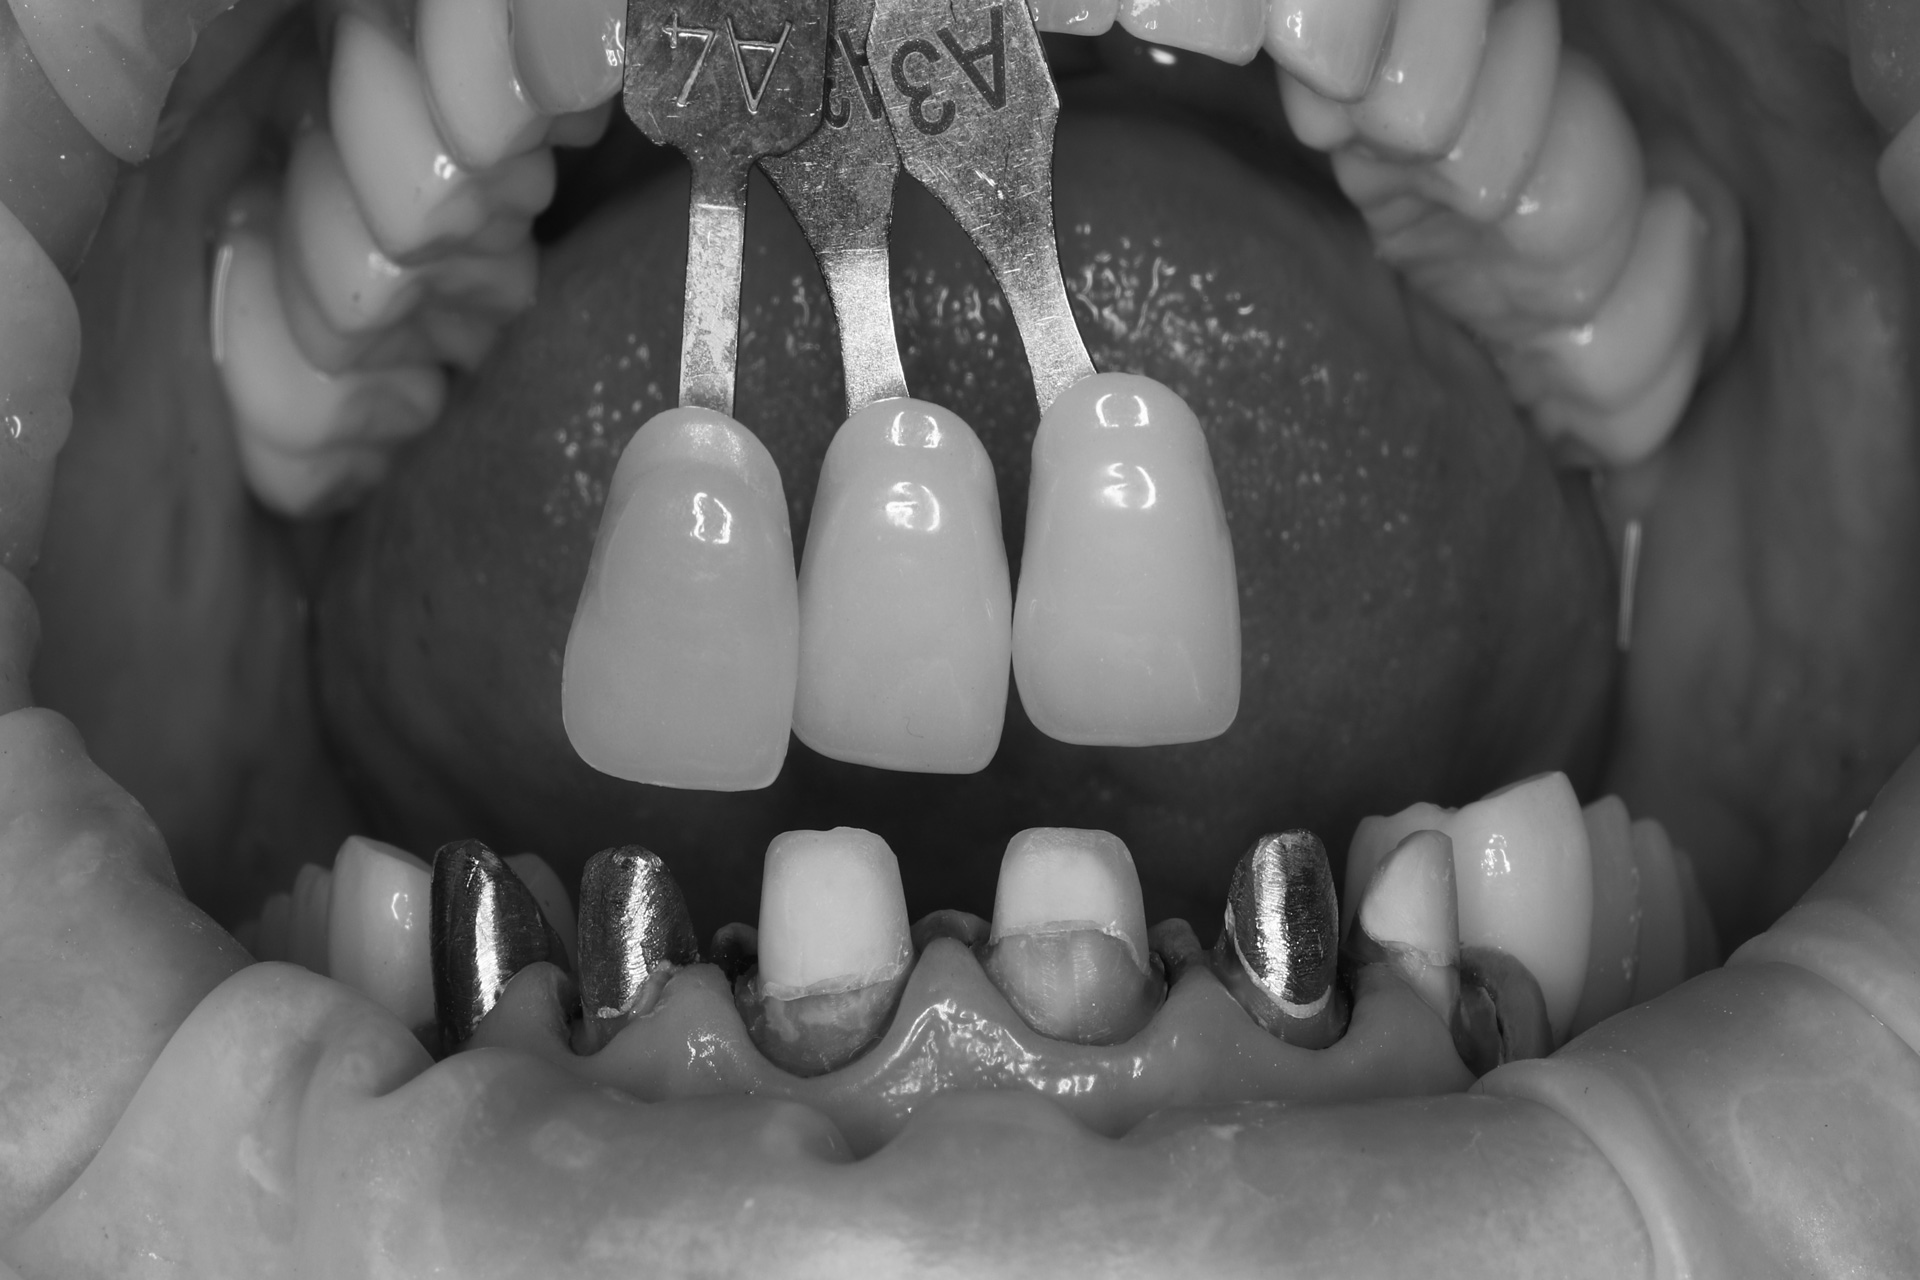

І настала війна… Після 1,5 року ми зустрілись знову. А частини тимчасових зубів вже не було, але положення щелеп та імплантанти збереглись. Тому дуже швидко перевели роботу з тимчасових коронок на постійні. Загалом було встановлено всі види ортопедичних конструкцій: коронки, вініри та керамічні накладки.